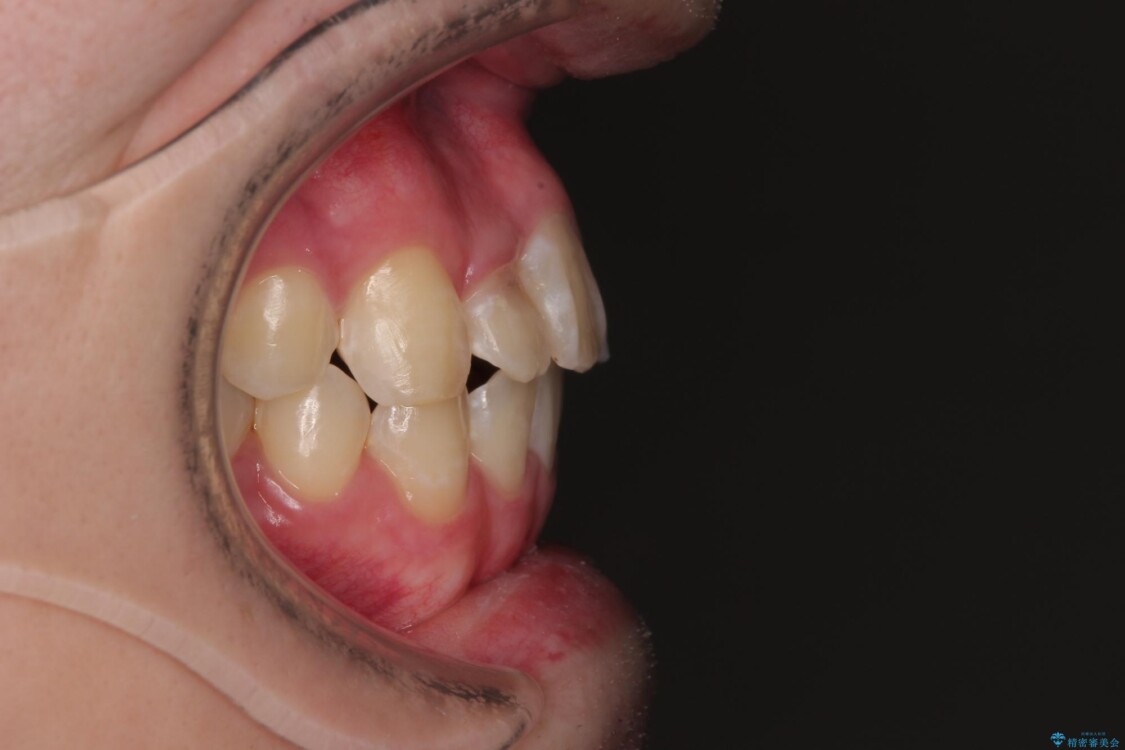

「歯並びがデコボコしていて、上下の中心がズレているのが気になる…」という悩みで来院された患者さまの症例をご紹介します。

初診時の状態

・上下ともに歯がきれいに並びきらず、がたつきが見られました。

・上下の前歯の中心(正中)がずれています。

・特に上顎の幅が狭いため、下顎の歯列も内側に入り込み、歯が並ぶスペースが不足していました。

治療前

• 1年でここまで変わる!歯列のがたつきと正中のズレを改善した矯正治療(メタルブラケット×MARPE) 治療前画像